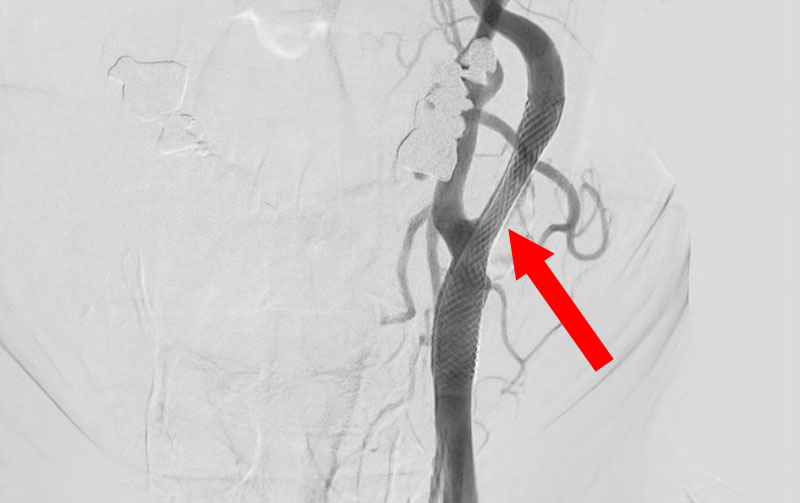

1619

'26年3月11日

左内頚動脈狭窄症

70代

大阪府の病院

手術写真

治療

前